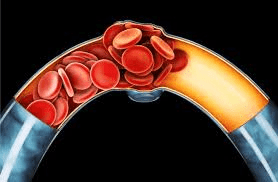

Artery blockages don’t appear overnight. They build slowly, quietly, and often without pain. That’s why many adults go years without realizing their arteries may be narrowing. The danger comes when cholesterol, inflammation, or plaque reduces blood flow.

When arteries narrow, blood has a harder time reaching your extremities. You might feel chilly fingers, tingling toes, or a persistent coolness that feels out of place. Many seniors think this is normal aging. But researchers suggest poor circulation may play a role.

5. Shortness of Breath During Simple Tasks

Poor circulation may delay wound healing. Something as small as a nick from trimming your nails can take surprisingly long to close. That slow process might reflect reduced blood flow to the skin.